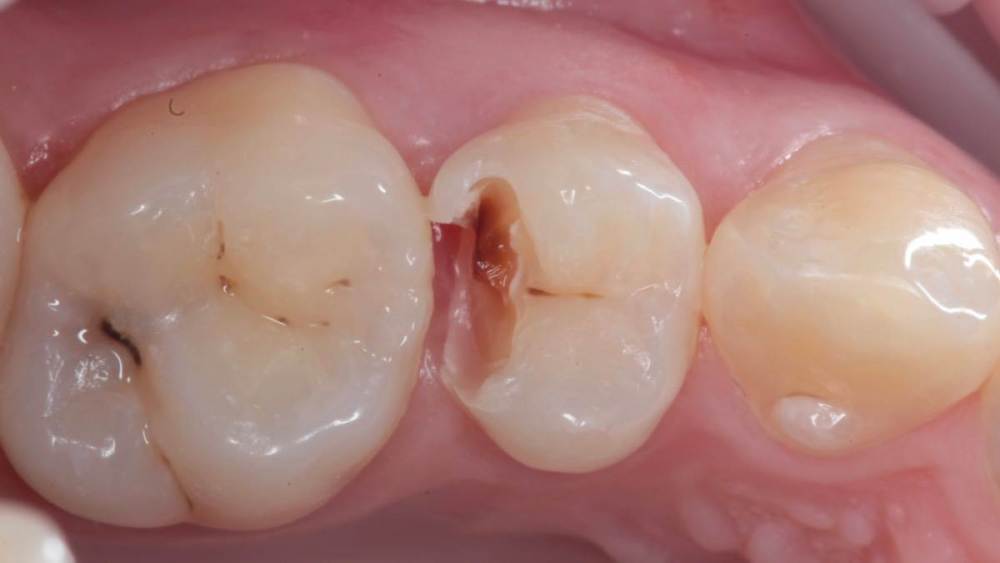

Гарриевич Опубликовано 21 мая, 2022 Поделиться Опубликовано 21 мая, 2022 (изменено) Будущее за регенеративной эндодонтией?) лечение в 2 посещения из-за нехватки времени (новый ассистент, перегруз пациентами, мысли о поднятии стоимости лечения, гипердиагностика?) глубокая пульпотомия, триоксидент, композит. фото подробно выложил это снимок с временной пломбой мало ли что вы подумаете Изменено 21 мая, 2022 пользователем Гарриевич 1 Ссылка на комментарий